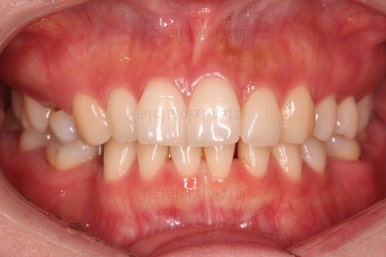

초진 시 입안의 모습인데요.

왜 그런지 비밀이 풀리는 것 같죠?

윗니는 한 쪽이 치아 2개가 결손이면서 유치가 하나 남아있고요.

아랫니는 한 쪽은 1개, 반대편은 2개 치아가 결손이었습니다.

도합 5개의 치아가 결손이었는데요.

결손 위치의 갯수가 위아래 좌우 다 달라서 중앙선이 맞을래야 맞을 수가 없는 상황이었죠.

결손치아 주위 치아들은 쓰러지고 비틀어져 있어서 장기적으로 좋지 못한 상황이었고요.

좀 더 디테일하게 윗니 작은 앞니 1개가 왜소치아라서 치아 크기도 맞지 않은 상황이었습니다.